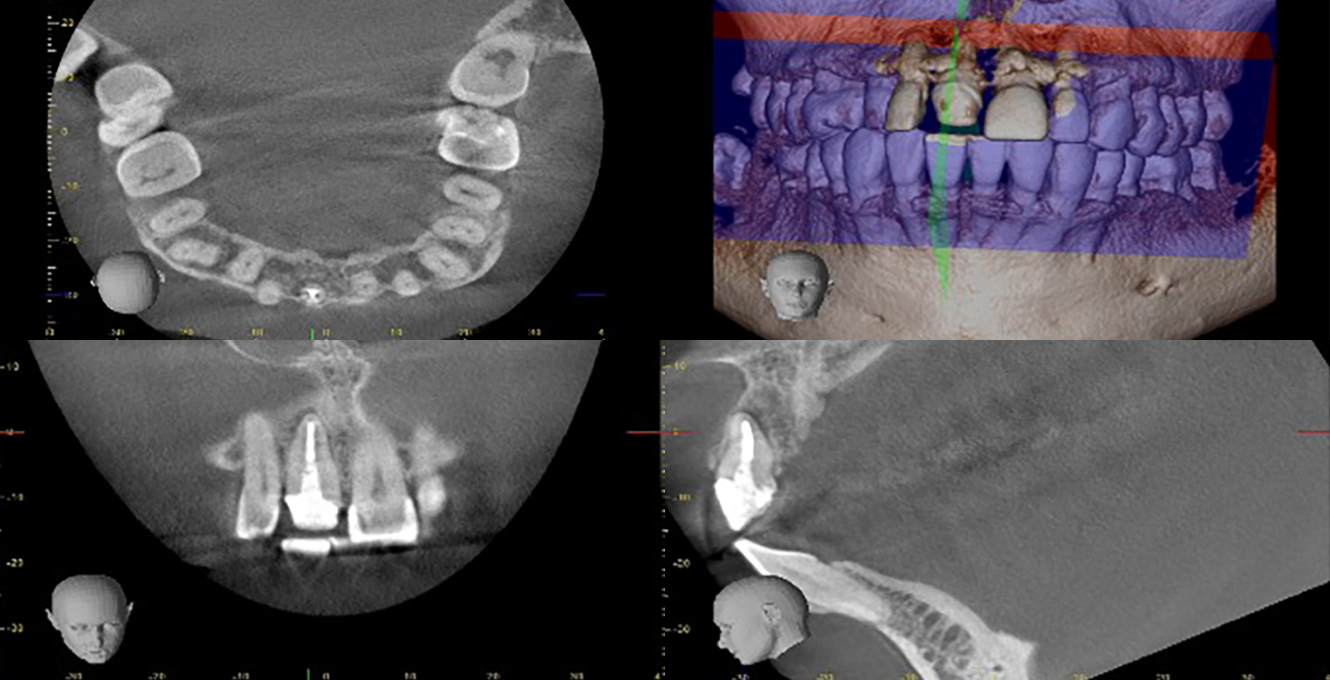

歯髄壊死と根尖性歯周炎、エンドペリオ病変

- 主訴

- 歯茎が腫れて、歯がぐらぐらする。噛むと痛い

- 治療内容

- 左下第二大臼歯

歯髄壊死(炎症によって、歯の中の血流が止まり、神経が壊死した状態)が生じ、それにより根尖性歯周炎と歯内歯周病変(エンドペリオ病変)に達した状態

大きな充填物の下で虫歯になり、そこから歯髄への感染、炎症が生じた症例。

強い炎症によって、炎症が根管内だけに留まらず、周囲の骨まで炎症が波及している。

また、辺縁骨まで炎症と骨破壊が進行し、深い歯周ポケット(>9mm)と同部位から膿が出ていた。

炎症と病状の進行度は極めて深刻で、根管治療によって、炎症のコントロールと周囲骨の再生が期待できるかどうかは、治療をしてみないとわからない状態からのスタートでした。

- 治療期間

- 2回

- 治療のリスク

- 根管治療によって、感染のコントロールができるかどうか。

炎症は、根管内だけに留まらず、広範囲の歯周周囲骨まで広がり、歯周病まで引き起こしているので、それら全てを改善し、骨が再生できるかどうか。

結果的に根管治療を行なっても、治療の効果がなく抜歯になる可能性を患者様とよく相談する必要があった。

結果は、周囲骨の再生を認め、治療としては成功し、歯を保存することができたが、患者様の口腔内の清掃状態が良好であったことや、全身疾患がなかったこと、さまざまな面でプラスに働く要素があったことも成功の大きな要因でありました。

BEFORE

AFTER